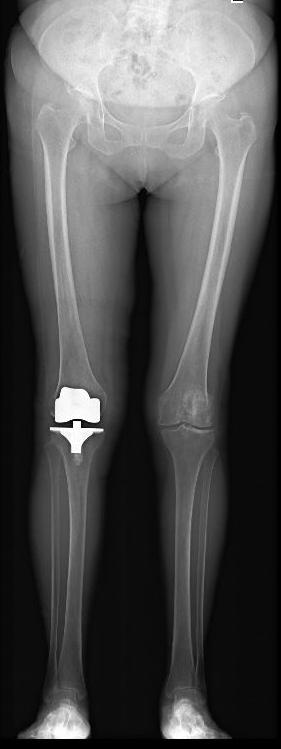

图7 膝骨关节炎全膝关节表面置换术a术前

图7 膝骨关节炎全膝关节表面置换术b术后

图7 :a图示双膝骨关节炎严重、外翻畸形。b图示右侧全膝关节表面置换术后